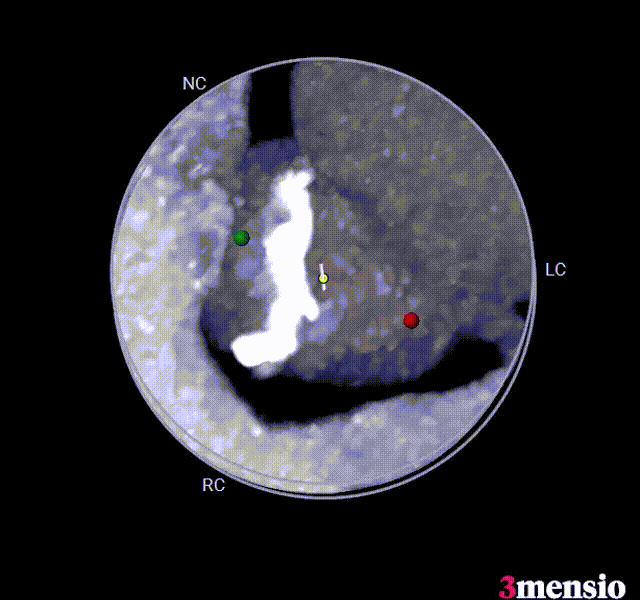

Type 0型二叶瓣,小瓣环,流出道偏小,轻度钙化,钙化主要分布在大弯侧瓣叶边缘,瓣上限制轻

主动脉瓣根部概览

主动脉瓣根部钙化概览

左冠开口低,左侧瓣叶偏长,窦部空间可,冠脉遮挡风险不高